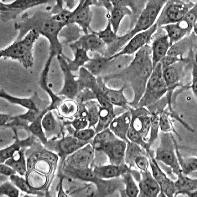

BT-20

Морфология:

эпителиоподобная

Способ культивирования:

монослойный